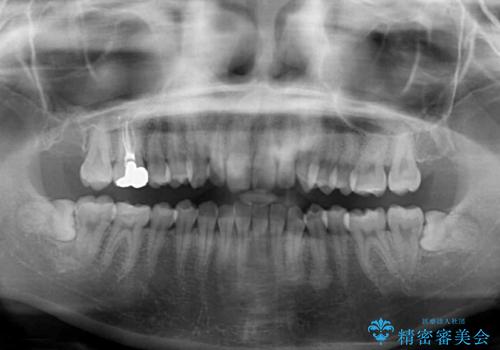

上下ともにデコボコの程度は著しいものではなく、インビザラインで十分に対応可能な歯列不正でした。

後戻りによりスペースができてしまうことを避ける目的で、IPR(歯と歯の間を削る)を極力用いない矯正治療を行うこととしました。

- 近々転勤の予定があるが、早めにインビザラインによる矯正治療を始めたいとのことで来院された患者様です。